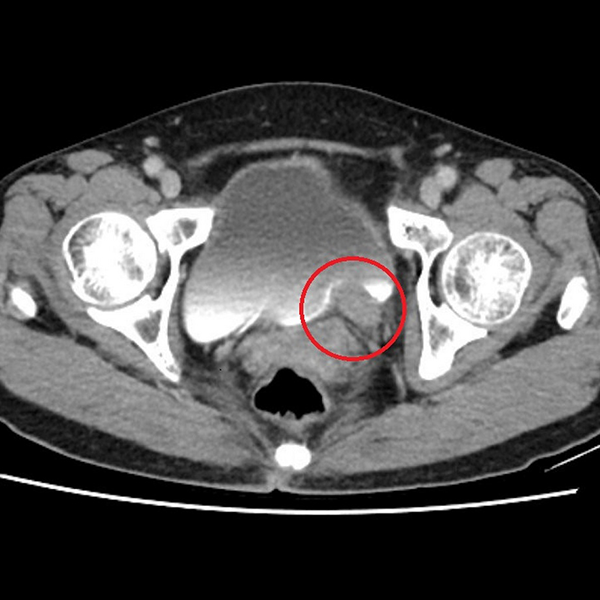

在探討海芙刀這項革新技術之前,我們必須先理解將這股浪潮引入台灣的第一人,鄭丞傑醫師。他不僅是一位日復一日面對病患的資深婦科醫師,其影響力更已擴展至亞洲乃至全球的消融醫學領域。

這份權威性,建立在他於專業領域的實際貢獻之上:

在台灣:作為台灣婦科腫瘤消融醫學會的創會理事長,他主導建立了本土的學術交流平台,透過舉辦年會與國際研討會,凝聚專家共識,致力於提升國內的治療水平與標準化。

在亞洲:擔任亞太婦科腫瘤消融學會理事長,他積極促進亞太各國醫師間的技術合作與經驗分享,鞏固了台灣在該領域的樞紐地位。

在全球:出任世界消融醫學會的婦科委員會主席,他更代表著婦科專業,在國際舞台上分享來自台灣的臨床數據與成功經驗,參與全球性的學術對話。

正是這份橫跨臨床、區域與世界的宏觀視野,讓鄭醫師能遠在十多年前便洞見婦科治療的未來趨勢。本篇文章,將帶您深入了解他如何將這份遠見化為真實的醫療服務,並透過「海芙刀」為無數女性開創了保留子宮、遠離手術恐懼的嶄新選擇。